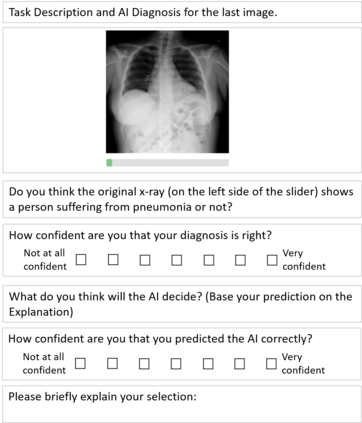

With the ongoing rise of machine learning, the need for methods for explaining decisions made by artificial intelligence systems is becoming a more and more important topic. Especially for image classification tasks, many state-of-the-art tools to explain such classifiers rely on visual highlighting of important areas of the input data. Contrary, counterfactual explanation systems try to enable a counterfactual reasoning by modifying the input image in a way such that the classifier would have made a different prediction. By doing so, the users of counterfactual explanation systems are equipped with a completely different kind of explanatory information. However, methods for generating realistic counterfactual explanations for image classifiers are still rare. Especially in medical contexts, where relevant information often consists of textural and structural information, high-quality counterfactual images have the potential to give meaningful insights into decision processes. In this work, we present GANterfactual, an approach to generate such counterfactual image explanations based on adversarial image-to-image translation techniques. Additionally, we conduct a user study to evaluate our approach in an exemplary medical use case. Our results show that, in the chosen medical use-case, counterfactual explanations lead to significantly better results regarding mental models, explanation satisfaction, trust, emotions, and self-efficacy than two state-of-the-art systems that work with saliency maps, namely LIME and LRP.